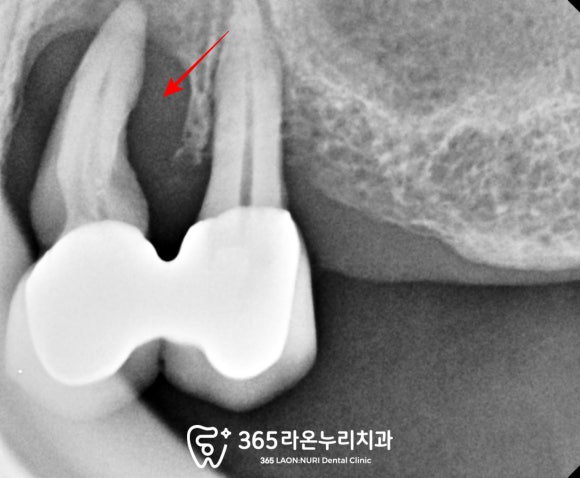

육안으로 발견하기 어려운

염증이나 잇몸뼈의 상태도

확인하기 위한 파노라마를 찍어보니

그 문제가 더 심각하네요.

보이는 것처럼

잇몸뼈가 뿌리 끝까지 녹아

큰 힘을 주지 않아도

금방 빠질 것만 같이

아슬아슬하게 느껴집니다.

또한 전반적으로 잇몸이 많이 내려가고

부러진 어금니도 있었습니다.